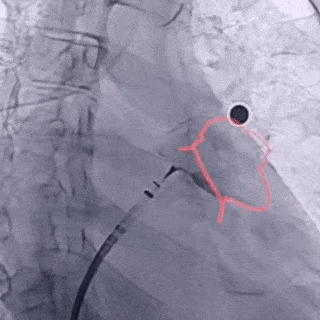

Seal 密封

代表密封,即观察封堵器密封情况,封堵完全,残余分流不超过5mm

肝位即刻造影,位置合适

上下缘无残余漏,形态位置良好

右肩位造影,无残余漏

封堵完全

正足位造影,上下缘无残余漏

封堵器释放后评估

符合PASS释放原则,释放封堵器

释放后造影,无残余分流

释放后封堵器形态良好,封堵完全

术中采用退鞘法进行封堵器展开,封堵器展开后肝位即刻造影,封堵器肩部位于左心耳开口处,位置合适,上下缘无造影剂漏;牵拉时有明显回弹,且牵拉后封堵器位置无移动;测量其压缩比为14.4%,符合PASS释放原则,释放后封堵器形态良好,位置稳定,造影无残余分流,无露肩。